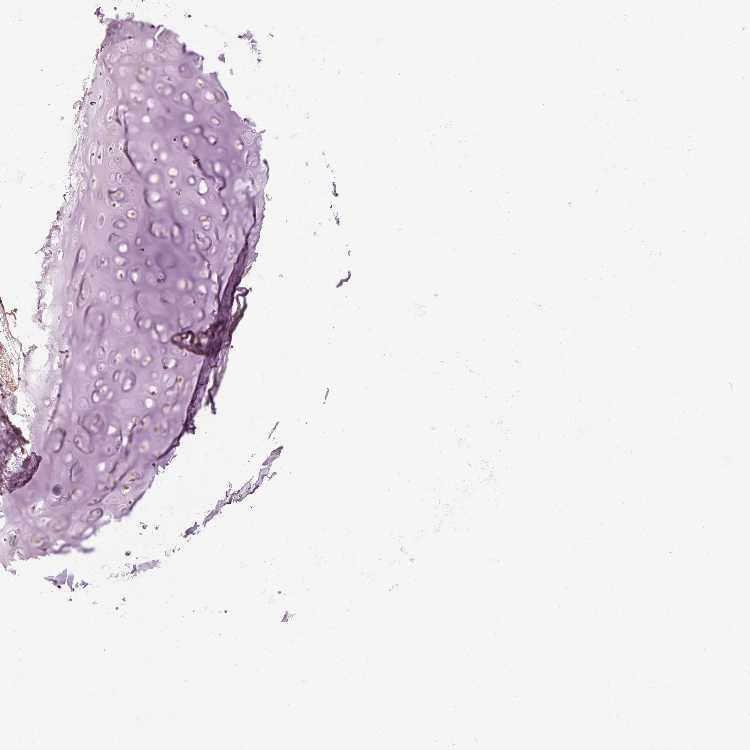

SOFT TISSUE 1 - Antibody stainingi

Antibody staining in the annotated cell types in the current human tissue is reported as not detected, low, medium, or high, based on conventional immunohistochemistry profiling in selected tissues. This score is based on the combination of the staining intensity and fraction of stained cells.

Each image is clickable and will lead to virtual microscopy that enables deeper exploration of all samples and also displays staining intensity scores, fraction scores and subcellular localization as well as patient and tissue information for each sample.

Antibody HPA036231Antibody HPA036232

Chondrocytes Not detectedLow

Fibroblasts Not detectedNot detected